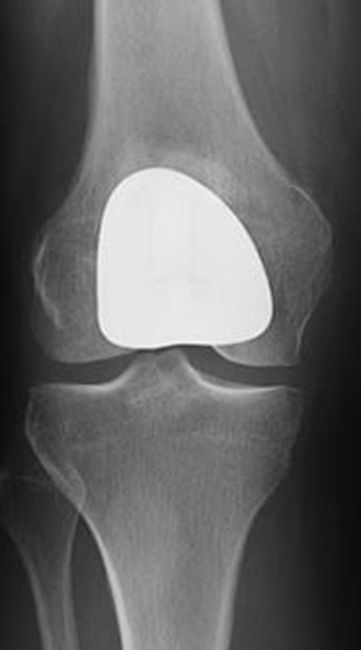

X-rays of knee before and after patellofemoral replacement

(Left) This X-ray is taken from above the knee. The patella and the trochlear groove of the femur have become deformed due to osteoarthritis. There is now bone rubbing on bone. (Right) The same knee after patellofemoral replacement. The patellar implant on the underside of the kneecap does not show in an X-ray.

Front view of a knee after patellofemoral replacement

Front view of a knee after patellofemoral replacement.